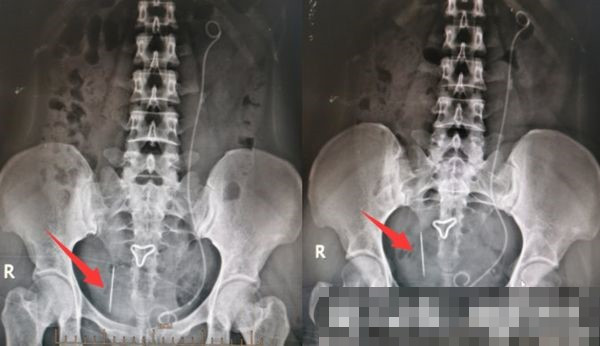

| Cây kim rỉ sét được lấy ra khỏi cơ thể cô Tiễn. |

Ngay sau đó, cô Tiễn được chỉ định phẫu thuật. Ca phẫu thuận diễn ra suôn sẻ, bác sĩ lấy ra chiếc kim thêu rỉ sét dài khoảng 3cm, khiến bản thân cô Tiễn cũng ngỡ ngàng.